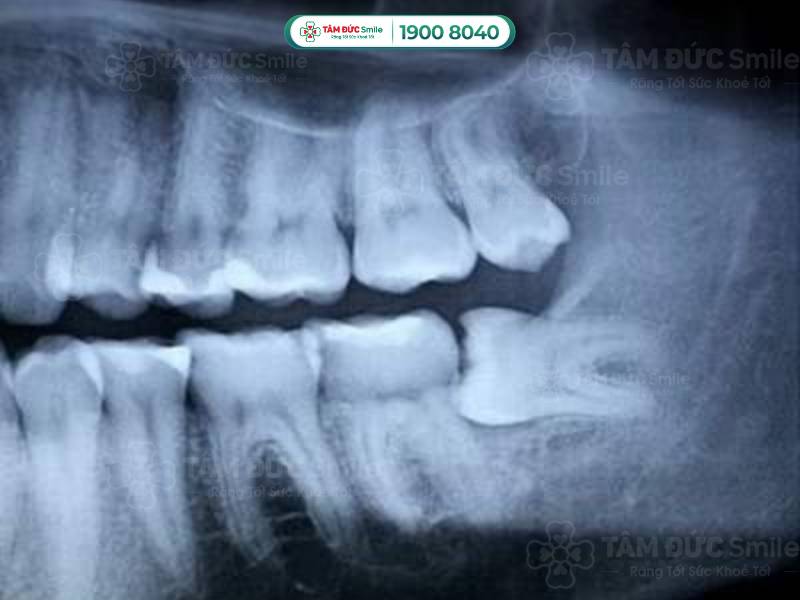

Răng khôn mọc ngang là tình trạng răng khôn mọc lệch so với vị trí bình thường. Thay vì mọc thẳng đứng, răng khôn mọc ngầm dưới nướu theo một góc 90 độ so với răng số 7. Mời Quý khách cùng tìm hiểu dấu hiệu nhận biết răng khôn mọc ngang và ảnh hưởng của nó ngay dưới đây.

Răng khôn mọc ngang khó nhìn thấy bằng mắt thường mà chủ yếu chẩn đoán qua phim chụp X-quang. Tuy nhiên, nếu có các dấu hiệu sau thì có khả năng răng khôn của Quý khách đang mọc ngang:

Răng khôn mọc ngang là tình trạng răng mọc nghiêng 1 góc 90 độ so với răng số 7

- Vị trí và hướng mọc của răng khôn: Bác sĩ sẽ chụp X-quang để xác định vị trí và hướng mọc của răng khôn. Răng khôn mọc ngang, chèn ép lên các răng khác hoặc nằm sâu trong xương hàm sẽ cần nhổ bỏ để tránh biến chứng. Độ phức tạp của ca nhổ răng cũng phụ thuộc vào vị trí và hướng mọc của răng.